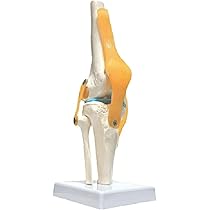

【爆買い!】 実物大 90cm 脊髄骨盤模型 人体模型 吊り下げ 後頭骨 台座付き 置物の詳細情報

人体模型 脊髄骨盤模型 90cm 実物大 吊り下げ 台座付き 後頭骨。人体模型 脊髄骨盤模型 90cm 実物大 吊り下げ 台座付き 後頭骨。Amazon.co.jp: UPstore 実物大 脊髄骨盤模型 90cm 背骨 脊柱模型。【R5年】新潟のお米 20kg【精米済み】。人体模型 脊椎骨盤模型 骨脊椎 せきつい 股関節あり45cm 1/2。脊椎模型 85cm 脊椎骨盤模型 脊柱模型 可動式 脊髄骨盤模型 人体。人体模型 脊髄骨盤模型 90cm 実物大 吊り下げ 台座付き\r\r【商品仕様】\r本体サイズ:32×24.5×88cm\r台座展示時:240×240×890mm\rセット内容:脊髄模型×1\r専用吊り下げ台×1\r材質:PVCプラスティック\rヘルニア病部(赤)も視覚で分かり易く設計されてます。\r\r脊柱模型が壊れたので新たに新品で2024年7月に購入したが、前の模型が直り、不要になったので出品します。\r写真の通り可動性がありますが、腰部の捻りが少し硬めです。\rほぼ未使用に近い商品ですが、神経質な方はご遠慮ください。\rご納得いただける方にお譲りします。。人体模型 脊椎骨盤模型 骨脊椎 せきつい 股関節あり45cm 1/2。Amazon.co.jp: 人体模型 人体骨格模型,靭帯再現・筋の着色。脊椎 模型 人体模型 1/2 脊椎骨盤 骨盤 骨 45センチ 脊髄骨盤。Amazon.co.jp: 人体模型 骨 等身大 脊椎 模型 実物大 90センチ。楽天市場】脊髄骨盤模型 90cm 吊り下げ 台座付きの通販。Amazon.co.jp: UPstore 実物大 脊髄骨盤模型 90cm 背骨 脊柱模型。脊椎模型 85cm 脊椎骨盤模型 脊柱模型 可動式 脊髄骨盤模型 人体